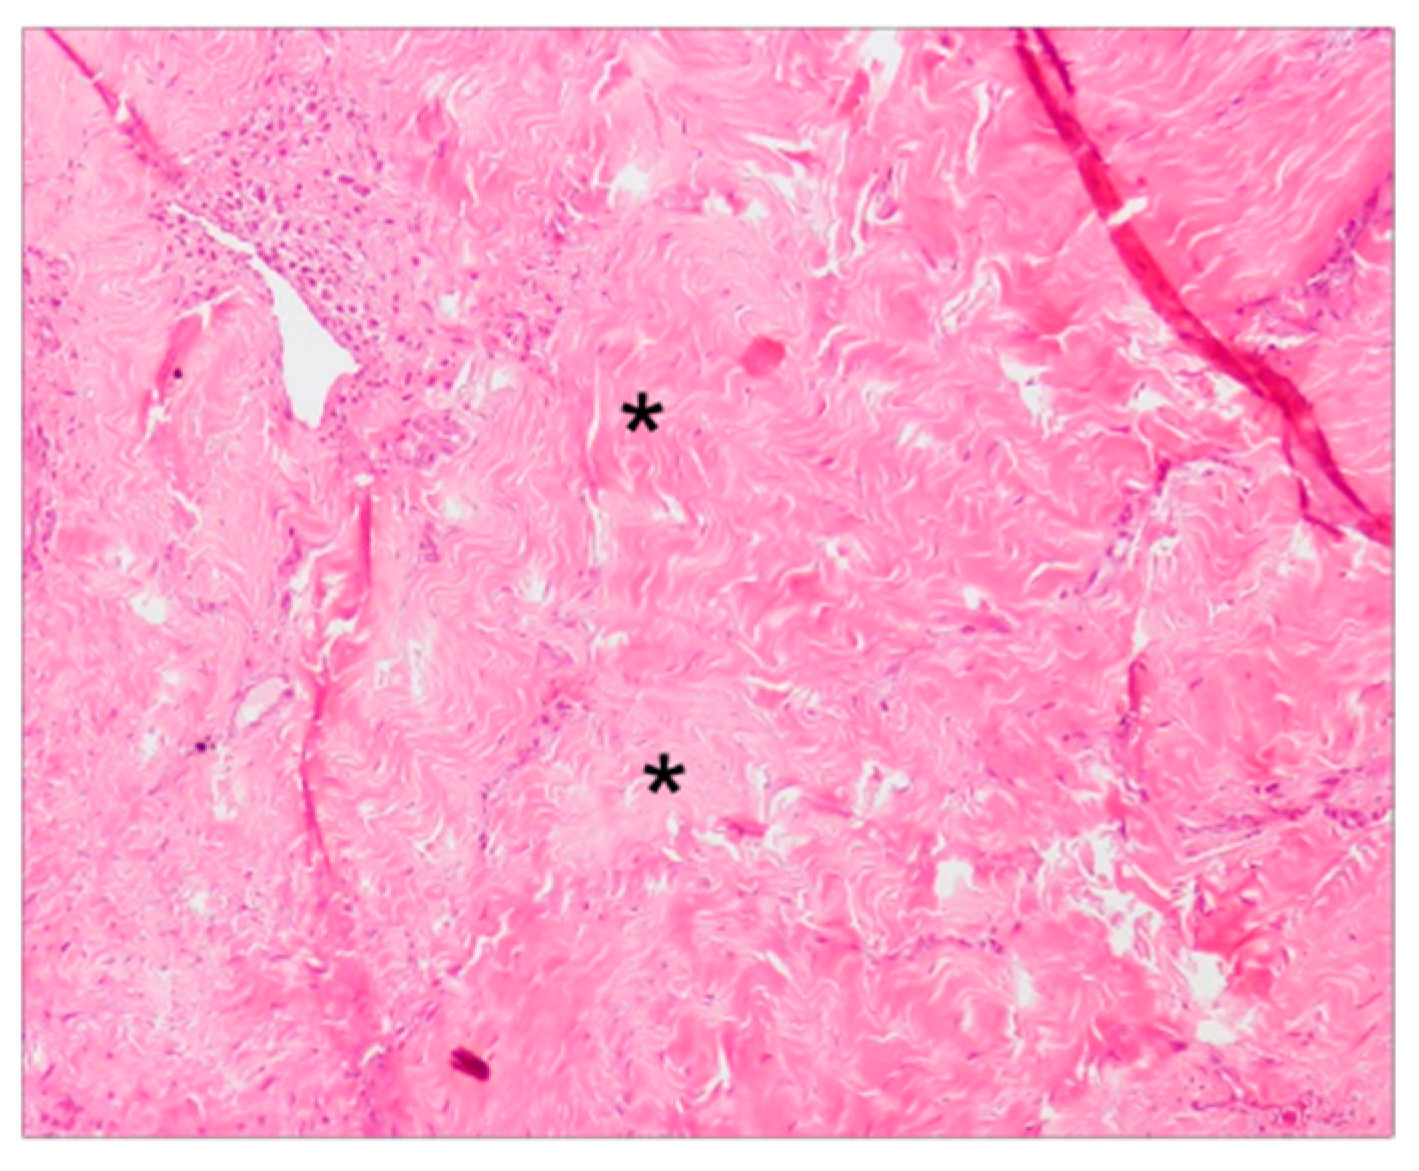

The collagen fibers maintained a normal orientation and a regular difference in density according with their position in the connective tissue. In particular, in the deep layer of the sub-epithelial connective tissue, collagen fibers were denser and more parallel to the gingival epithelium. The less numerous and thinner fibers of the superficial layer showed a “sunburst” pattern with respect to the root surface and the alveolar bone but with a perpendicular fashion related to the gingival lining epithelium (Figure 2a). In the superficial layer of the connective tissue there were elongated capillaries, while in the deep layer there were arterioles with orientation parallel to the collagen fibers. Particular aspects could be found in the increased number and size of the deep collagen fibers, due to a substantial sclerotization (Figure 5), and the lower laxity of the superficial ones. Moreover, in the sclerotic areas, a reduced number of vessels were present.

Figure 5. Light microscopy of 4 µm sections showing the substantial sclerotization of the deep collagen fibers, at a magnification of 10×. * = sclerotic areas.